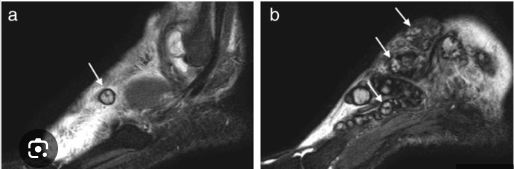

Hình 8. Dấu chấm đen trong vòng tròn (“dot-in-circle” sign) trên tổn thương u nấm ở hệ cơ xương trên phim chụp MRI và siêu âm

Hình 9. Sagital T1 (2A), Coronal T2 (2B): cho thấy các thay đổi viêm trên bàn chân trái với nhiều thương tổn nhỏ rải rác, thâm nhiễm mô mềm bàn chân và kéo dài lên đến xương. Tổn thương được mô tả như các thương tổn có tín hiệu cường độ cao và vòng tín hiệu kém ở ngoại vi và các chấm tín hiệu kém ở trung tâm (peripheral low-signal rim and low-signal dot in the center) được mô tả với tên gọi là chấm trong vòng tròn (“dot in circle” sign) (xem mũi tên đỏ). hình ảnh Coronal T1 sau bơm thuốc guadolinium (2C±2D) thấy tăng độ rõ nét của tổn thương và sự tồn tại các ổ tín hiệu kém, nhỏ được bao quanh bởi mô có cường độ tín hiệu thấp (mũi tên đỏ).  |